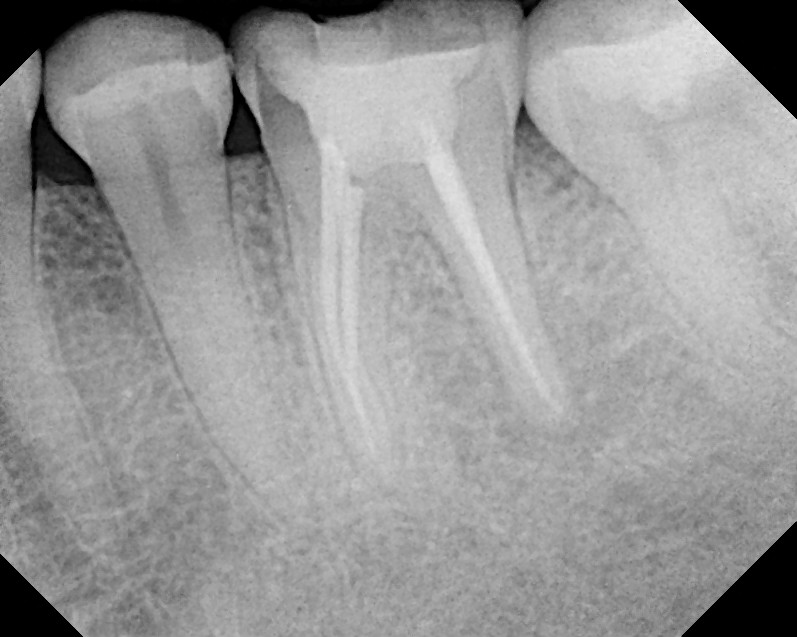

Фиброзный апикальный периодонтит: Причины и лечение